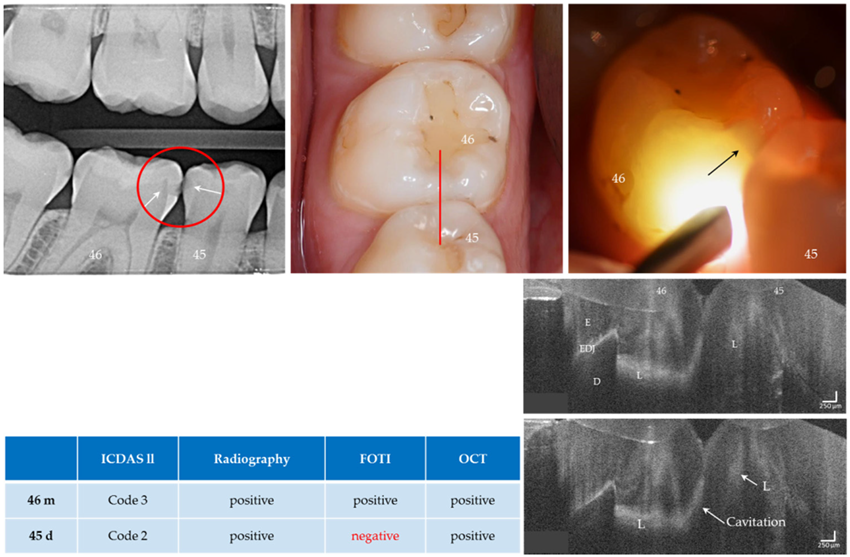

Figure 11.

Teeth 46 (m) and 45 (d). Both surfaces showed visual and radiographic caries lesions (L, arrows) and dentin involvement was visible on tooth 46. The FOTI showed no signal on tooth 45 distally (arrow indicates the lesion of tooth 46), while a weak signal was visible on OCT. In the OCT images of tooth 46, dentin involvement is clearly visible and cavitation can be assumed due to the diagonal signal line (see Fig. 5b) and the anatomy of the tooth surface. Verification: Both the early carious lesion on tooth 45 and the cavitated lesion on tooth 46 could be confirmed later during the restoration of tooth 46. Enamel (E), dentin (D), enamel-dentin junction (EDJ). The vertical scales are related to refractive index n = 1.5.